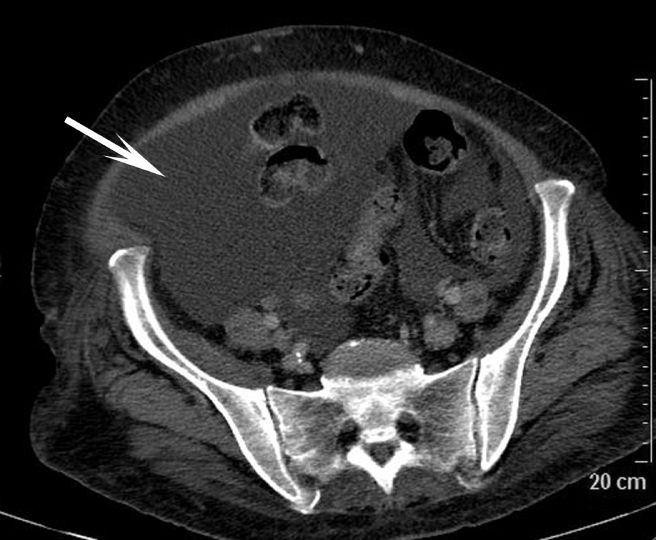

Au scanner, l’ascite apparaît comme un épanchement de densité liquidienne (entre 0 et environ 30 UH) ne se rehaussant pas après injection de produit de contraste (figures 4.2 et 4.3). En IRM, l’ascite présente un hypersignal en pondération T2, un hyposignal en pondération T1 qui ne se rehausse pas après injection (cf. figure 16.3).

Fig. 4.2 Coupe tomodensitométrique axiale de l’étage pelvien montrant une ascite abondante (flèche) au sein de laquelle s’observent les anses digestives.

Source : CERF, CNEBMN, 2022.